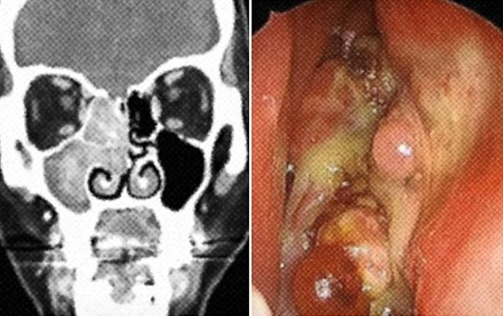

✔ 비강 내시경 검사로 비강과 부비동 내부를 직접 관찰합니다.

✔ 컴퓨터단층촬영(CT)과 자기공명영상(MRI)으로 종양의 크기, 위치, 주변 침범 여부를 평가합니다.